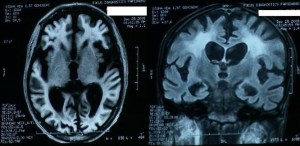

We present serial MRI studies in the case of a 45-year-old man who sustained an in hospital cardiac arrest and was successfully resuscitated after 25 minutes of cardiopulmonary resuscitation. Five years after the cardiac arrest he remains in a persistent vegetative state. Serial MRI studies (Fig 1 immediately and Fig 2 after 3 years and Fig 3 after 5 years of cardiac arrest) indicate ongoing cerebral atrophy and highlight the delayed effects of an initial anoxic injury.

Serial MRI axial and coronal sections studies (Fig 1 immediately and Fig 2 after 3 years and Fig 3 after 5 years of cardiac arrest) indicate ongoing cerebral atrophy and highlight the delayed effects of an initial anoxic injury.